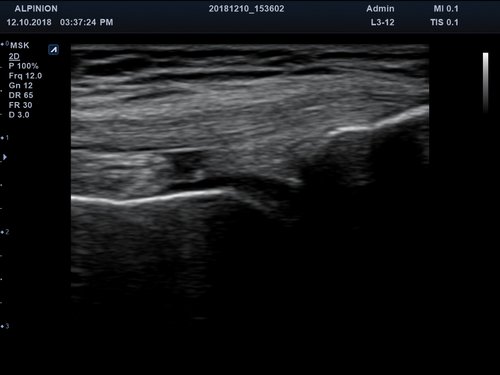

• MSK

Anwendungsbereiche Abdomen MSK, Nerven, Karotis, periphere Gefäße, Schilddrüse, Mamma

Bildgebungs-Modi B-Modus, CF, M, PW, PD B-Modus, CF, M, PW, PD

• B-Modus: Darstellung zweidimensionale Bilder anatomischer Strukturen